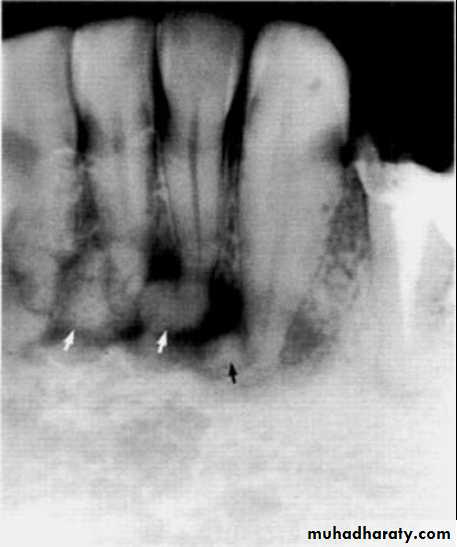

Periapical Cemento-osseous Dysplasia

Site: Apices of vital lower incisor teeth.Shape: — Round, monolocular

— Often multiple.

Outline: —Poorly defined

— Not corticated.

Radiodensity: — Early stage — radiolucent

— Intermediate stage — radiolucent with patchy opacity within the radiolucency

— Late stage — densely radiopaque but surrounded by a thin radiolucent line.